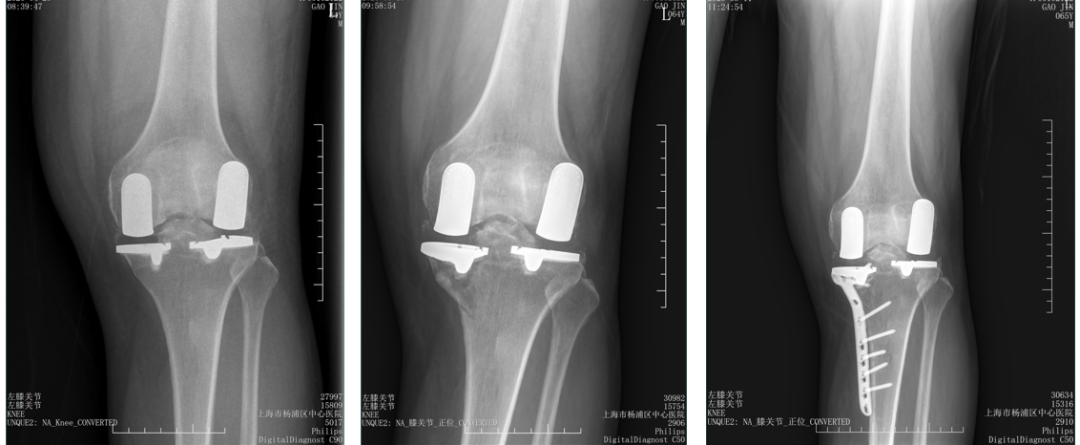

双间室OA行Bi-UKA术后内侧假体周围骨折ORIF

六、二期双单髁置换LINK:registered: SLED假体位置

1、内侧UKA术后外侧间室进展性OA

2、外侧UKA术后内侧间室进展性OA

3、内侧UKA术后外侧进展OA行Bi-UKA术后内侧垫片脱位

MUKA外侧OA进展行Bi-UKA术后内侧Bearing脱位翻修